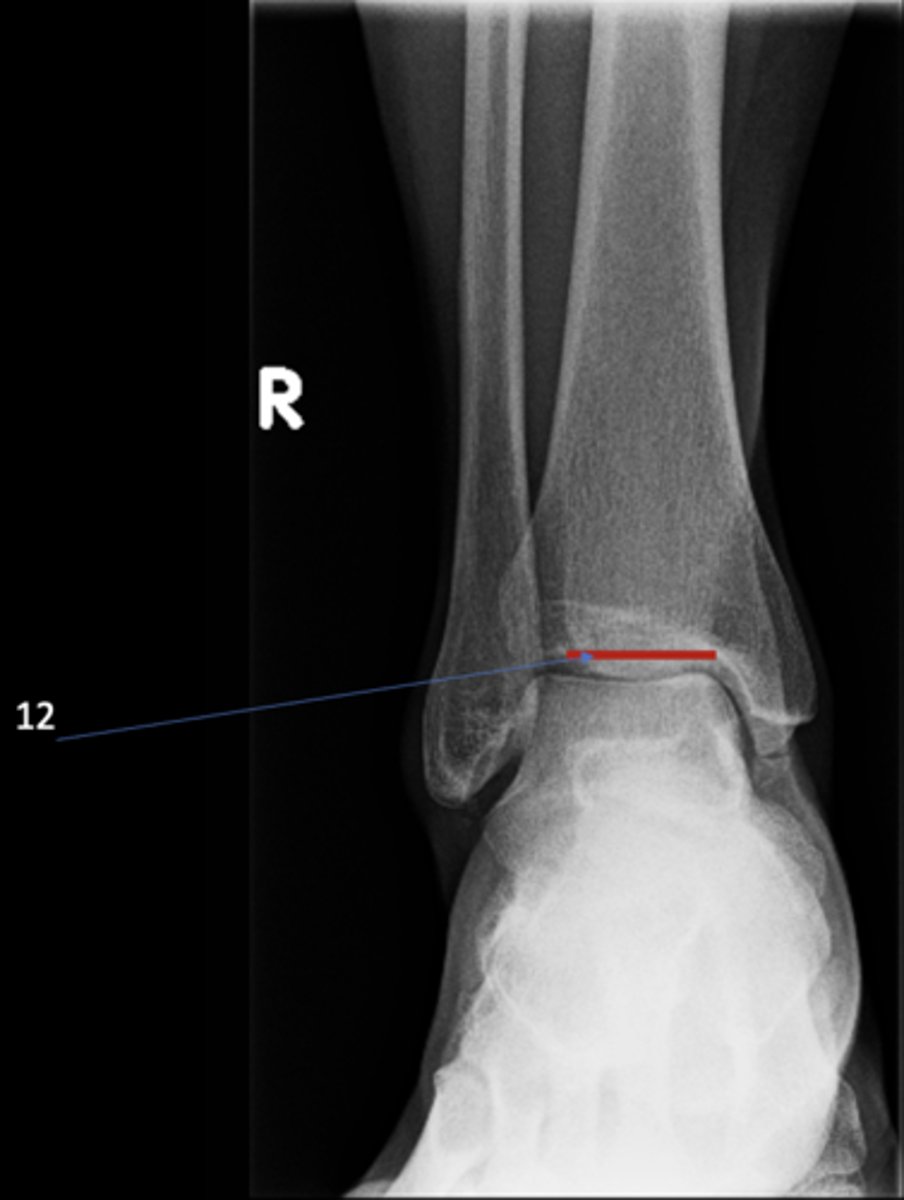

Right posterior superior iliac spine

ID 11

<p>ID 11</p>

12

New cards

Left femoral neck

ID 12

<p>ID 12</p>

13

Left anterior inferior iliac spine

ID 13

<p>ID 13</p>